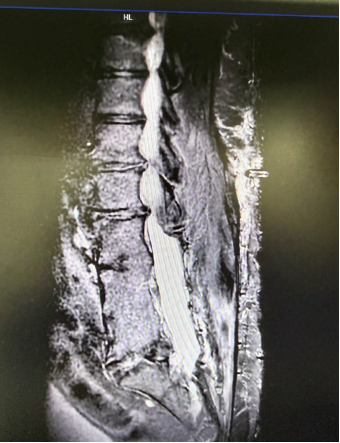

Patient's Preoperative MRI

Upon admission, the Pain Management team

conducted a comprehensive and systematic evaluation of the patient. Integrating

his medical history, clinical manifestations, and imaging findings, they

organized a multidisciplinary consultation and discussion. The team identified

significant anatomical abnormalities in the surgical area, including

postoperative scar adhesions and severe spinal canal stenosis, which

substantially increased the technical difficulty and procedural risks of